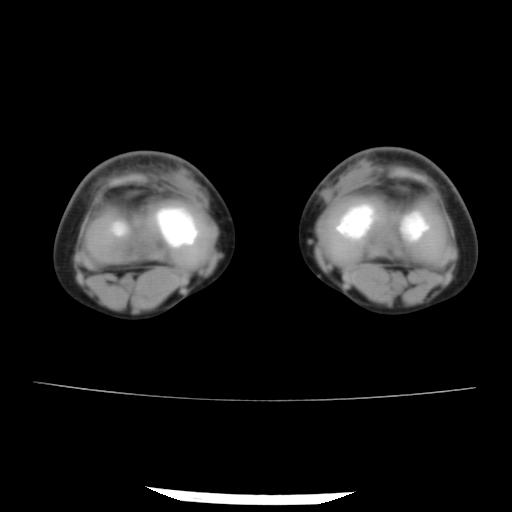

标题: PED0931:男,5岁,发现双小腿软组织肿块1年,质地中等,无 [打印本页]

标题: PED0931:男,5岁,发现双小腿软组织肿块1年,质地中等,无